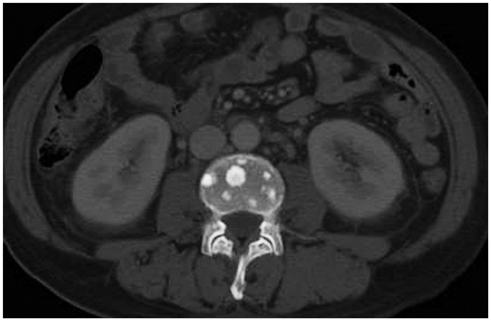

Figure